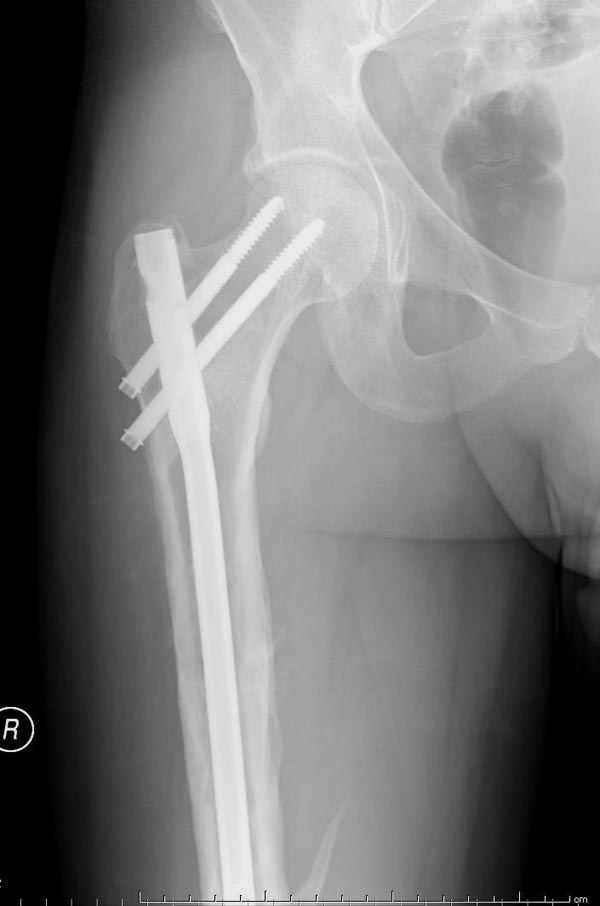

Представляю снимки больного с политравмой: леченного в другом мед.учреждении по поводу открытого перелома бедра, сперва аппаратом наружной фиксации, затем пластиной. Обратился к нам через 8 месяцев после удаления пластины с проблемой несросщего перелома бедренной кости, без клинических проявлении к инфицированию (не все снимки сохранены)

Рутинный интрамедуллярный остеосинтез с расверливанием и с фиксацией реконструктивным трокантерик штифтом (рис №1, №2),

если первые 4 месяца послеоперационного периода проходил без проблем, но на 5 месяце появились боли в дистальном отделе бедра и температура, т.е. симптомы медуллярного инфицирования (рис №3, №4).